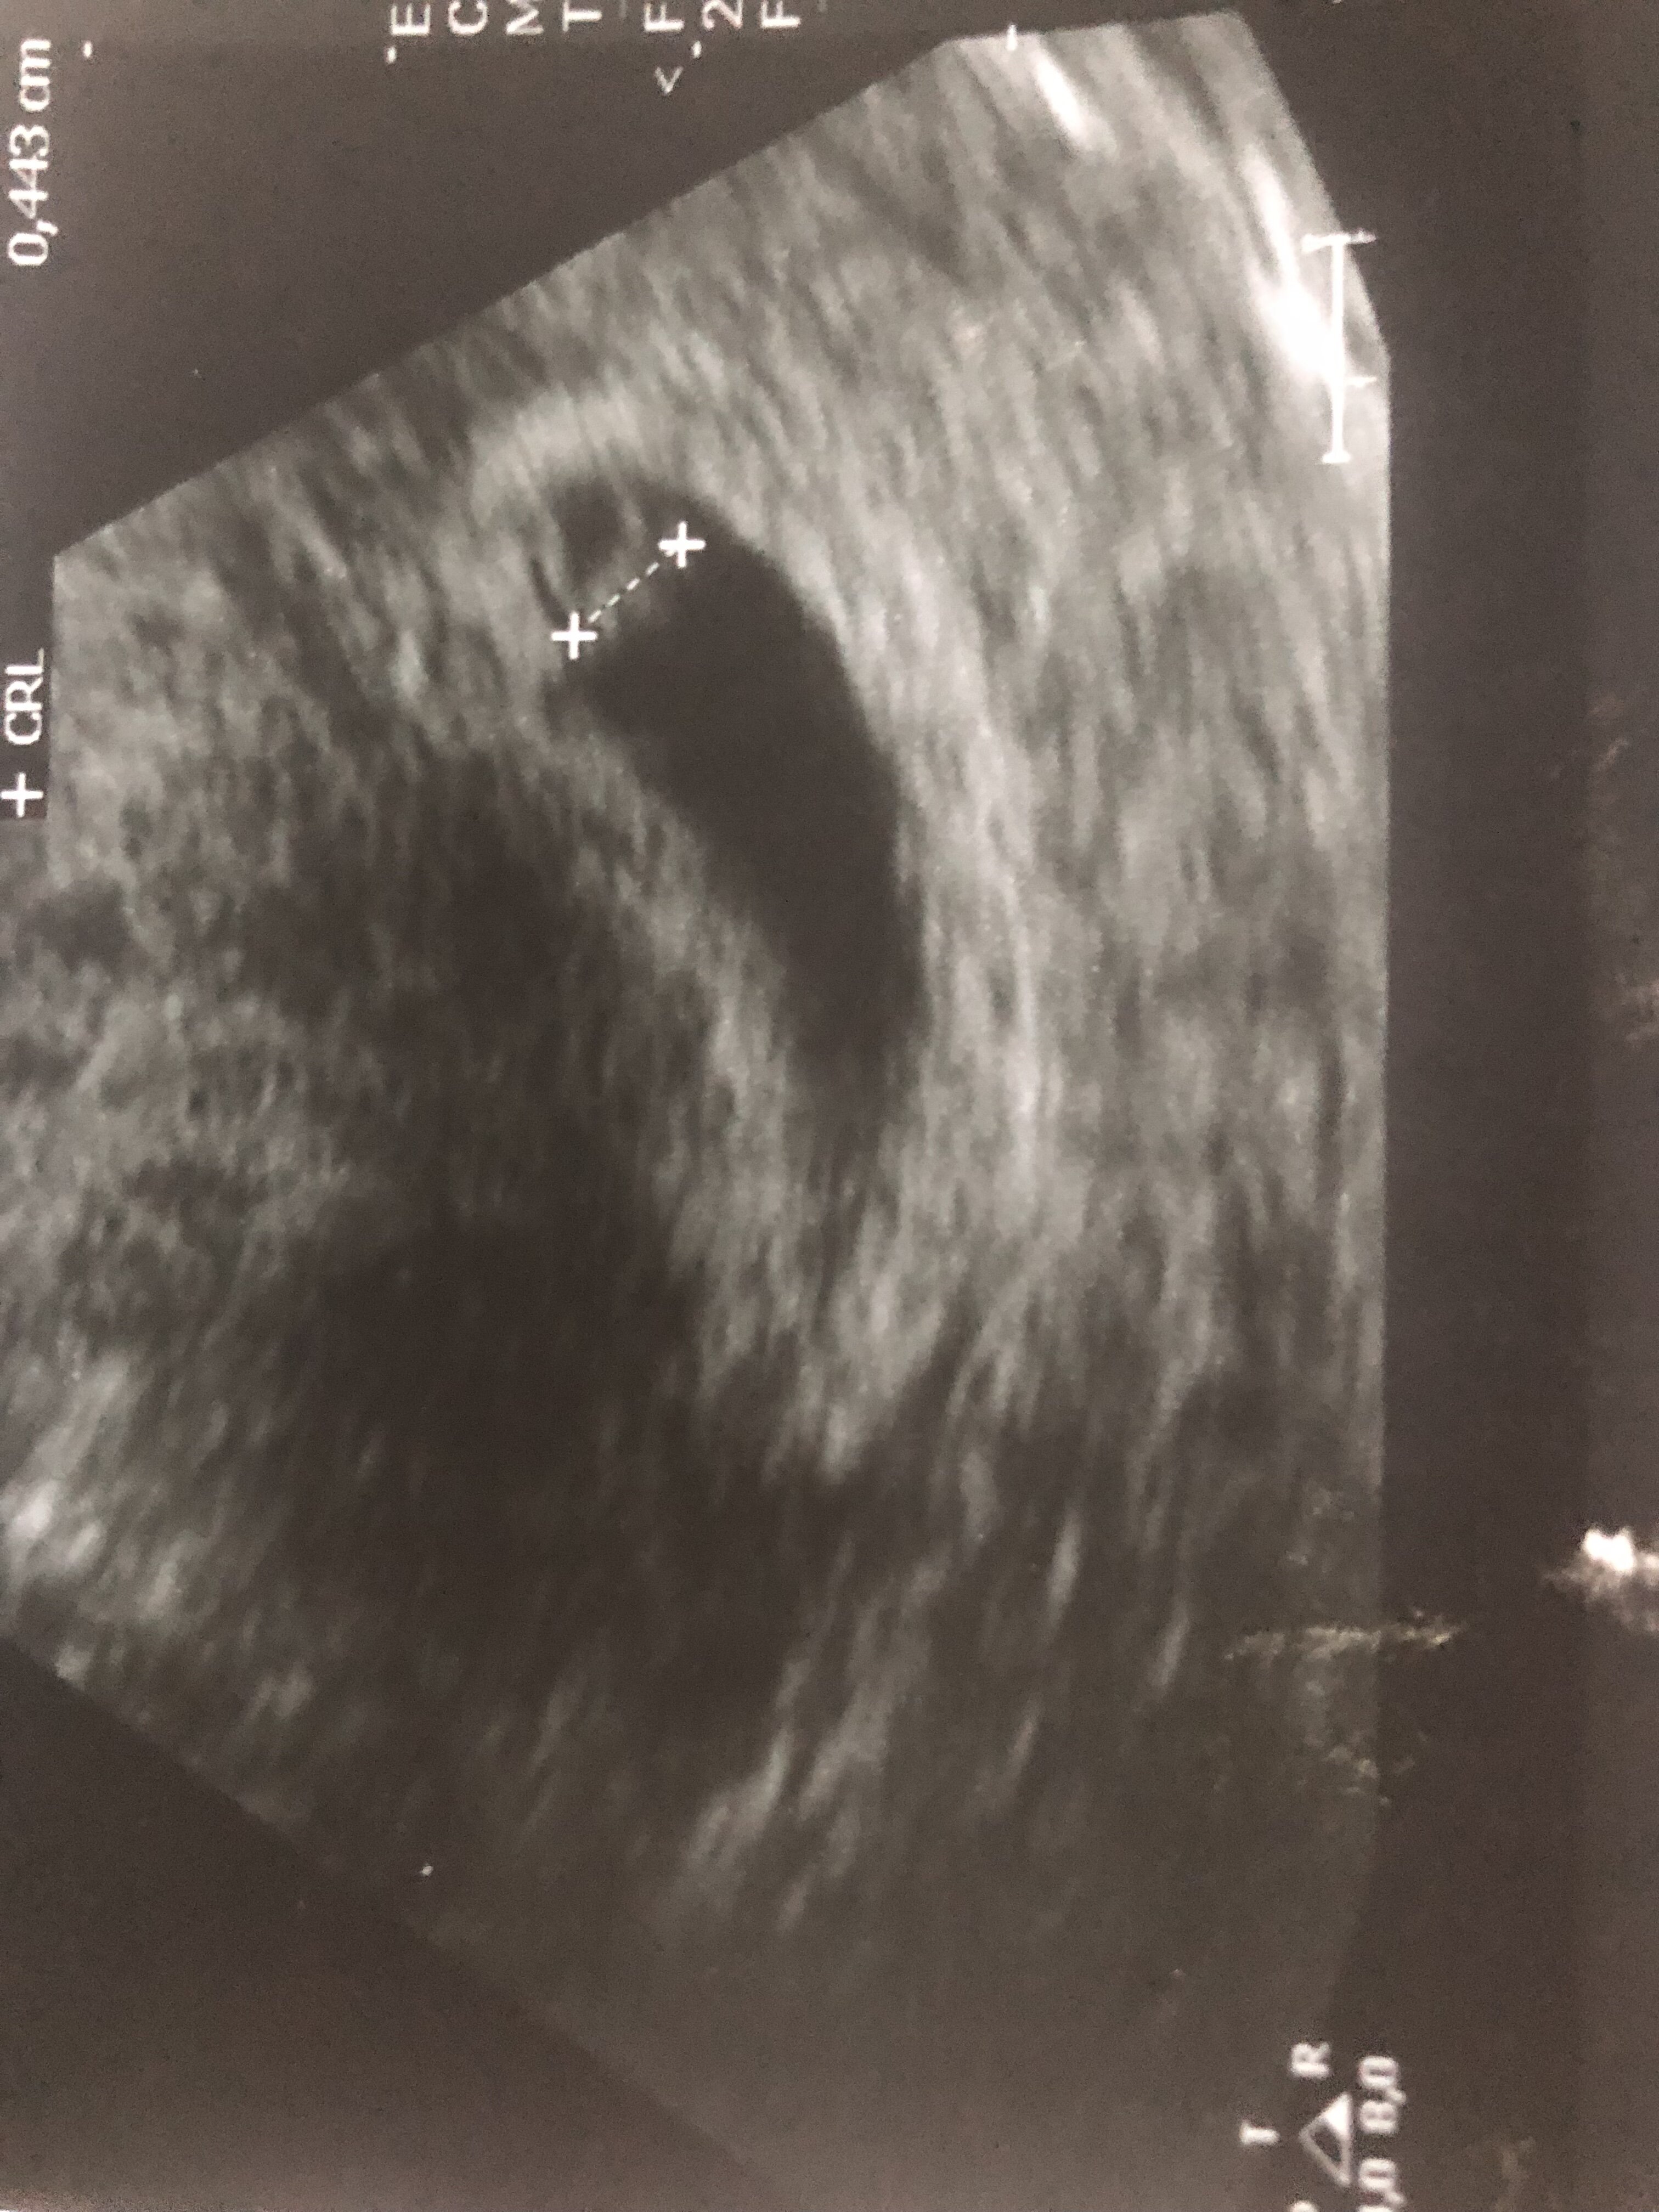

Dziewczyny, tak jeszcze patrzę na to swoje pierwsze usg (w 4 tc je miałam), gdzie lekarka znalazła 0.5mm pęcherzyk w macicy. Nie wiem czemu mam wciąż wątpliwości, ale mam troszeczkę zrytą psychikę po ostatniej ciąży pozamacicznej i jak mnie zaboli po jednej stronie, to znowu wpadam w panikę. Czy tak wygląda taki maluteńki pęcherzyk?

Może któraś też poszła wcześniej do ginekologa i miała podobny?